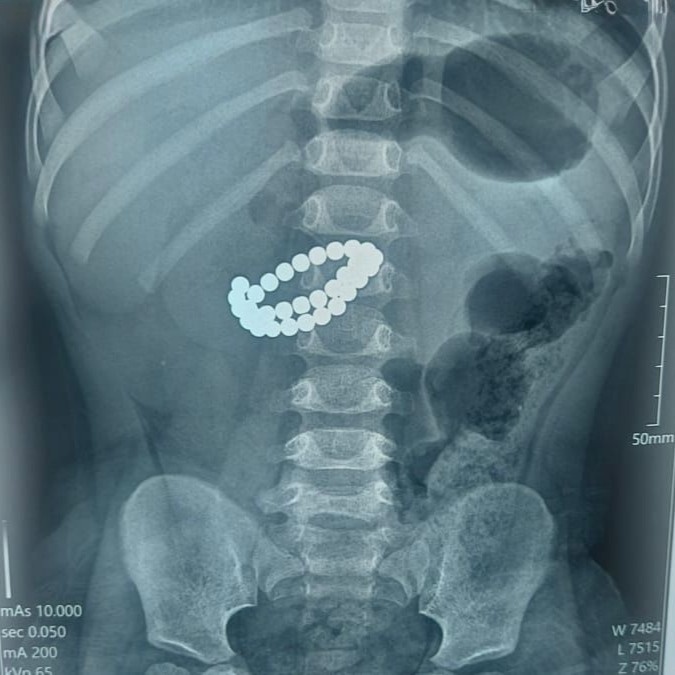

Алматыда екі жасар бала 31 магнит жұтып қойған

Қалалық қоғамдық денсаулық сақтау басқармасының хабарлауынша, қабылдау бөліміне 1 жас 9 айлық бала өте ауыр жағдайда жеткізілген. Тексеру нәтижесінде дәрігерлер «ішектегі бөгде заттар – 31 магнит, жіңішке ішектің көптік тесілуі, жайылған нәжістік перитонит» диагнозын қойды.

– Баланың өмірін сақтап қалудың жалғыз жолы – шұғыл хирургиялық ота жасау болды. Дәрігерлер ортаңғы лапаротомия жасап, құрсақ қуысы ағзаларына толық тексеру жүргізді. Ота барысында магниттер ішектен алынып, жіңішке ішектегі көптеген тесік тігілді, құрсақ қуысы тазартылып, дренаж орнатылды. Сонымен қатар ішекке трансаналдық интубация жасалды, - делінген хабарламада.

Фото: Алматы қоғамдық денсаулық сақтау басқармасы

Орталық хирургі Асқар Ризвановтың айтуынша, магниттердің басты қаупі – олардың ағзаға бөлек-бөлек түскенімен, ішекте бір-біріне тартылып, ішек қабырғасын қысып қалуында.

– Магниттердің арасында ішек қабырғасы қысылады, қан айналымы бұзылады, тіндер жансызданады, тесік пайда болады. Соның салдарынан санаулы сағаттардың ішінде перитонит дамуы мүмкін. Ата-аналар көбіне баланың жағдайы қаншалықты жылдам нашарлайтынын аңғармай қалады, - деді хирург.